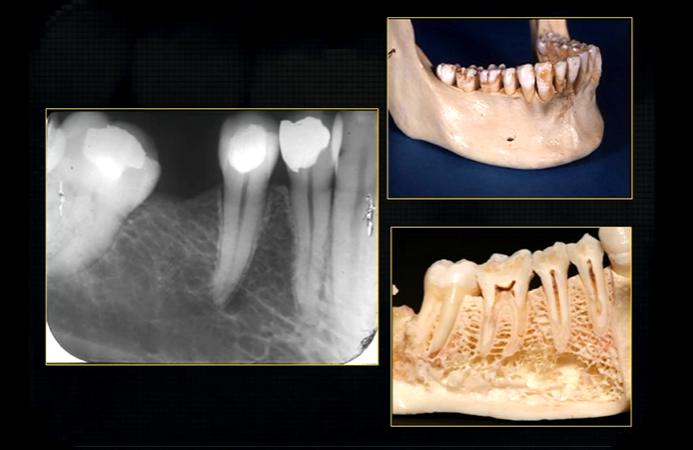

mental foramen - black radiolucency - near 1st and 2nd premolars

sockets of the teeth are represented by thin, white, opaque lines → ‘ lamina dura’

dense, white, radiopaque line → dense bone of mylohyoid ridge

underneath mylohyoid ridge - looks more radiolucent → this is due to the lingual indentation of submandibular fossa

dense cortical bone of the lower border

radiolucent band around the posterior part of the body of the mandible

created by inferior dental nerve and blood vessel, created by the inferior dental canal

the edges of the canal can be seen as thin, white radiopaque lines → ‘tram lines’

inferior dental canal can easily be seen in cross sectional dental images